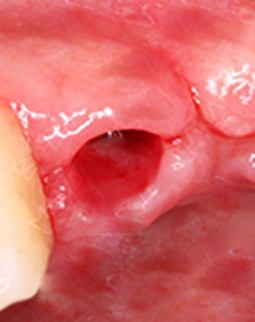

左边是我种牙之前,缺牙很久了,所以这个牙床口长好了。右边是我的种植牙创口,大小和牙根差不多,这个很容易理解,因为种植体就是人造牙根,得有个洞才能把它埋进去,我种牙的创口很小了,基本是微创的,比起过去的切开牙龈种牙好太多了!所以大家不用太担心,你选个好的医院和医生,种植牙还是很靠谱的。